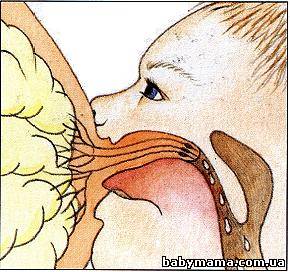

Почему, собственно, ассиметричное? Ребенок сцеживает молоко из груди волнообразными движеними язычка. Все подвижные, «рабочие» части ротика (язык, нижняя челюсть) находятся снизу. Поэтому очень важно, чтоб со стороны нижней челюсти в рот ребенку попал как можно больший участок ареолы. Из-за такой ассиметрии ротика ребенка хорошее прикладывание тоже будет ассиметричным.

От того, как ребенок возьмет грудь, насколько глубоко у него в ротике окажется сосок и ареола (темный околососковый кружок), зависит и безболезненное кормление, и отсутствие трещин, и набор веса, и количество молока.

Чуть наклоните голову вперед. Попробуйте широко открыть рот. Неудобно, правда? Заметьте положение языка — он приподнялся и находится далеко за деснами. А для сосания груди необходимо, чтоб язычок был над нижней десной, прикрывая ее сверху и охватывая грудь.

А теперь представим, что нам надо укусить яблоко, висящее на уровне нашего носа: чуть приподнимаем голову… Заметьте, как широко получилось открыть рот. Да и с высовыванием языка — никаких проблем. Обеспечьте и малышу такое положение, чтобы он мог выпрямить шею и широко раскрыть рот. Не давите ему на затылок, дайте опору спинке и шее.

Теперь у ребенка грудь глубоко в ротике, сосок там, внутри, касается границы твердого и мягкого неба. Обратите внимание, что снизу ареола глубже в ротике, чем сверху. Ребенок так плотно прижат к маме, что ей сверху видно только щечку, плотно прижатую к груди. Если на секунду слегка отодвинуть малыша от груди, станет заметно, что его губки развернуты, нижняя губа полностью отогнута. угол между верхней и нижней губой — не меньше 140°. А если уж совсем полюбопытствовать, и аккуратно отодвинуть уголок рта, будет виден язычок, охватывающий грудь.

Когда малыш сосет грудь правильно, его щечки надуты, а не втянуты. Подбородок глубоко упирается в мамину грудь. Носик может либо быть в стороне, либо слегка касаться груди. В таком случае малыш все равно успешно дышит, через маленькие треугольные щелочки между грудью и крыльями носа. Если кроха сильно упирается носом и ему все-таки неудобно дышать — скорее всего, его подбородок расположен недостаточно близко к маминой груди, а голова наклонена вперед. В таком случае не надо делать ямку в груди пальцем, надо сместить всего малыша назад, в направлении его ножек и плотнее прижать к себе. Его шейка выпрямится, подбородок глубже упрется в грудь, а носик освободится. Если чувствуете, что ребенок при этом захватил грудь неглубоко, лучше аккуратно забрать у него грудь (разжав пальцем десенки, чтобы не повредить сосок), и приложить его еще раз

Посмотрите, как происходит процесс выработки молока и кормления.